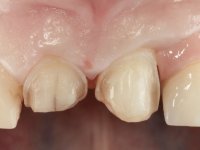

A paciente queixava-se que tinha um dente da frente a abanar, não gostava do “canino escuro” e também “queria fechar os espaços entre os dentes”. Passados 8 anos do tratamento inicial, o que motivou uma segunda fase de tratamento foi os “dois dentes da frente estarem feios”. Um ano após a última intervenção, apareceu um terceiro motivo para a terceira fase de tratamento, que foi a fratura da faceta feldspática colocada no dente 2.1.

Paciente do sexo feminino, com 47 anos não fumadora. Apresentou-se na consulta com o dente 1.3 com tratamento endodôntico e com um espigão falso coto fundido, reabilitado com uma coroa provisória. Os dois incisivos laterais superiores são conoides e de reduzida dimensão. O dente 2.2 apresenta mobilidade, consentânea com uma significativa reabsorção óssea entre o dente 2.1 e o dente 2.3 Os dois incisivos centrais estão separados por um diastema de 3mm e o dente 2.3 apresenta uma oclusão cruzada com o dente antagonista. Verifica-se também a ausência de alguns dentes posteriores e uma higiene oral razoável. Na segunda intervenção realizada passados 8 anos, verificou-se que os incisivos centrais superiores se apresentavam cromaticamente mais escuros e apresentavam um sulco longitudinal no esmalte que estando pigmentado comprometia esteticamente o sorriso. O trabalho realizado na primeira fase do tratamento mostrava-se competente estética e funcionalmente. Por fim, um ano após a última intervenção, a paciente apresentou-se com uma fratura da faceta colocada no dente 2.1 provavelmente em resultado de estar em contacto com o coto do implante. A rigidez da anquilose implantar, pode ter sido a causa desta fratura. Outros casos deste tipo de fratura já foram observados por mim em situações clínicas idênticas. A faceta do dente 1.2 apresentava-se esteticamente comprometida e a própria estrutura dentária apresentava uma pequena cárie e, pelo que se recomendaria a sua substituição.

Oito anos depois, na segunda intervenção, foi proposto o seguinte tratamento:

• Reabitação dos dentes Incisivos Centrais Superiores com facetas de cerâmica feldspática.